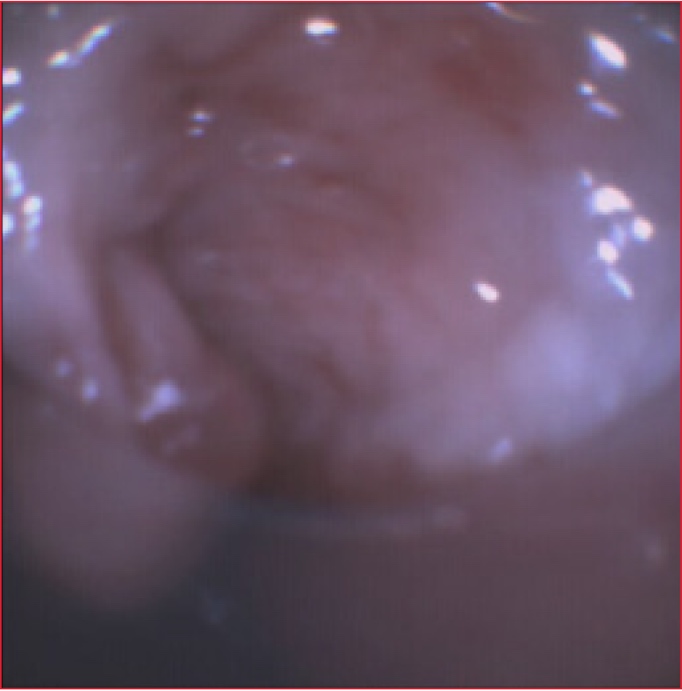

La broncoscopia flexible que se realizó por la cánula de traqueostomía mostró una membrana grisácea y anular que estaba adherida a la pared traqueal posterior a nivel del extremo distal de la cánula de traqueostomía (Figura 1). Además, se visualizaba un sector desprendido que se movía libremente en la vía aérea con el ciclo respiratorio para obstruir casi por completo la cánula de traqueostomía en forma de válvula (Figura 2). Ante la imposibilidad de aspirarlo, se decidió asegurar la vía aérea mediante la intubación endotraqueal. Al retirar la cánula, se extrajo parte de la seudomembrana.

Figura 1. Evaluación endoscópica realizada por la cánula de traqueostomía. Se observa una seudomembrana grisácea adherida a la pared posterior de la tráquea.

Figura 2. Sector móvil de la seudomembrana que obstruye intermitentemente la luz de la cánula de traqueostomía.